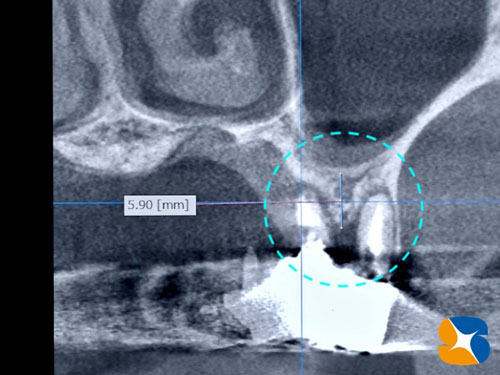

CT撮影の結果、銀歯の根が割れていることが判明しました。歯茎の腫れを治すには抜歯の必要性があります。さらに、抜歯した後はどうされますか?

人工骨は、ソケットリフト(骨の厚みを6㎜→10㎜にボリュームアップ)にも活用しました。

・ソケットリフト(骨の厚みを6㎜→10㎜にボリュームアップ)